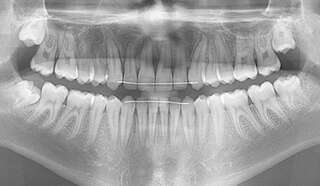

CANINES INCLUSES